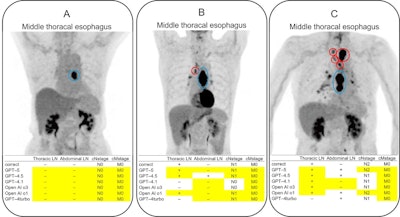

Examples of input images and responses of GPT-4.5, GPT-4.1, and OpenAI-o3 in cases of esophageal cancer. The primary tumor site indicated in the radiology report is shown as a blue circle, and the metastatic LNs are shown as red circles. Note that these colored circles were manually overlaid by the authors to visualize the ground truth and were not generated by the AI models. The yellow cells indicate the correct answers (agreement with the ground truth). (A) All the models correctly identified the absence of LN and distant metastases beyond the primary lesion. (B) A case with a single metastatic thoracic LN. Only GPT-5 and OpenAI-o1 provided a correct evaluation, identifying thoracic LN metastasis, no abdominal LN metastasis, and the correct cN and cM stages. Other models either failed to identify the thoracic LN metastasis or misdiagnosed abdominal LN metastasis as positive. (C) A cN-stage 2 case with thoracic LN metastasis. F-18 FDG accumulation in the hilar LNs was interpreted as nonspecific accumulation in the radiology report. GPT-5 correctly identified the cN stage but misdiagnosed abdominal LN metastasis as positive. Although other models correctly identified thoracic LN metastasis, many incorrectly stated the disease as N1.Examples of input images and responses of GPT-4.5, GPT-4.1, and OpenAI-o3 in cases of esophageal cancer. The primary tumor site indicated in the radiology report is shown as a blue circle, and the metastatic LNs are shown as red circles. Note that these colored circles were manually overlaid by the authors to visualize the ground truth and were not generated by the AI models. The yellow cells indicate the correct answers (agreement with the ground truth). (A) All the models correctly identified the absence of LN and distant metastases beyond the primary lesion. (B) A case with a single metastatic thoracic LN. Only GPT-5 and OpenAI-o1 provided a correct evaluation, identifying thoracic LN metastasis, no abdominal LN metastasis, and the correct cN and cM stages. Other models either failed to identify the thoracic LN metastasis or misdiagnosed abdominal LN metastasis as positive. (C) A cN-stage 2 case with thoracic LN metastasis. F-18 FDG accumulation in the hilar LNs was interpreted as nonspecific accumulation in the radiology report. GPT-5 correctly identified the cN stage but misdiagnosed abdominal LN metastasis as positive. Although other models correctly identified thoracic LN metastasis, many incorrectly stated the disease as N1. JMIR CancerAmong the LLMs, GPT-5 demonstrated the highest overall accuracy, with newer LLMs showing improved diagnostic accuracy when compared with previous models in identifying abdominal LN metastases and cM staging, though they showed weaker consistency for cN staging, the researchers added. For example, in thoracic LN detection, GPT-5 achieved 76 of 120 (63%) accuracy, whereas the other LLMs achieved 72 of 120 (60%) or lower accuracy.